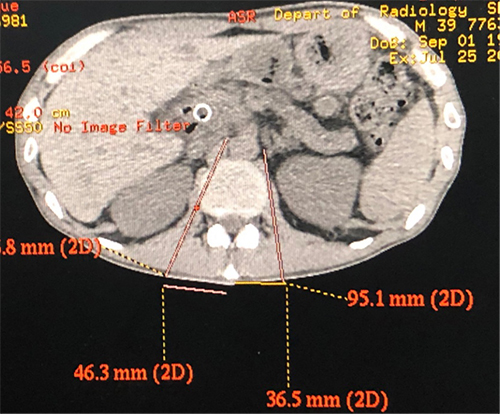

在医院影像科的配合下,疼痛科治疗团队通过CT设计穿刺进路,使得穿刺针到达了靶点位置。因患者曾经做过化疗和放疗,使得腹腔黏连加重,增加了手术难度,不利于毁损药物的扩散,但经过对穿刺针的反复调试,最终达到理想的效果。

腹腔神经丛毁损术是指将药物注入到腹腔神经丛所在部位,阻断支配内脏的交感神经,以缓解疼痛的一种方法。解剖学上,腹腔神经丛位于腹主动脉前缘,腹腔干及肠系膜上动脉之间。鉴于其周围有许多重要脏器结构,在CT引导下,穿刺针有效规避重要的脏器和血管精准到达神经丛。

CT协助下穿刺路径设计